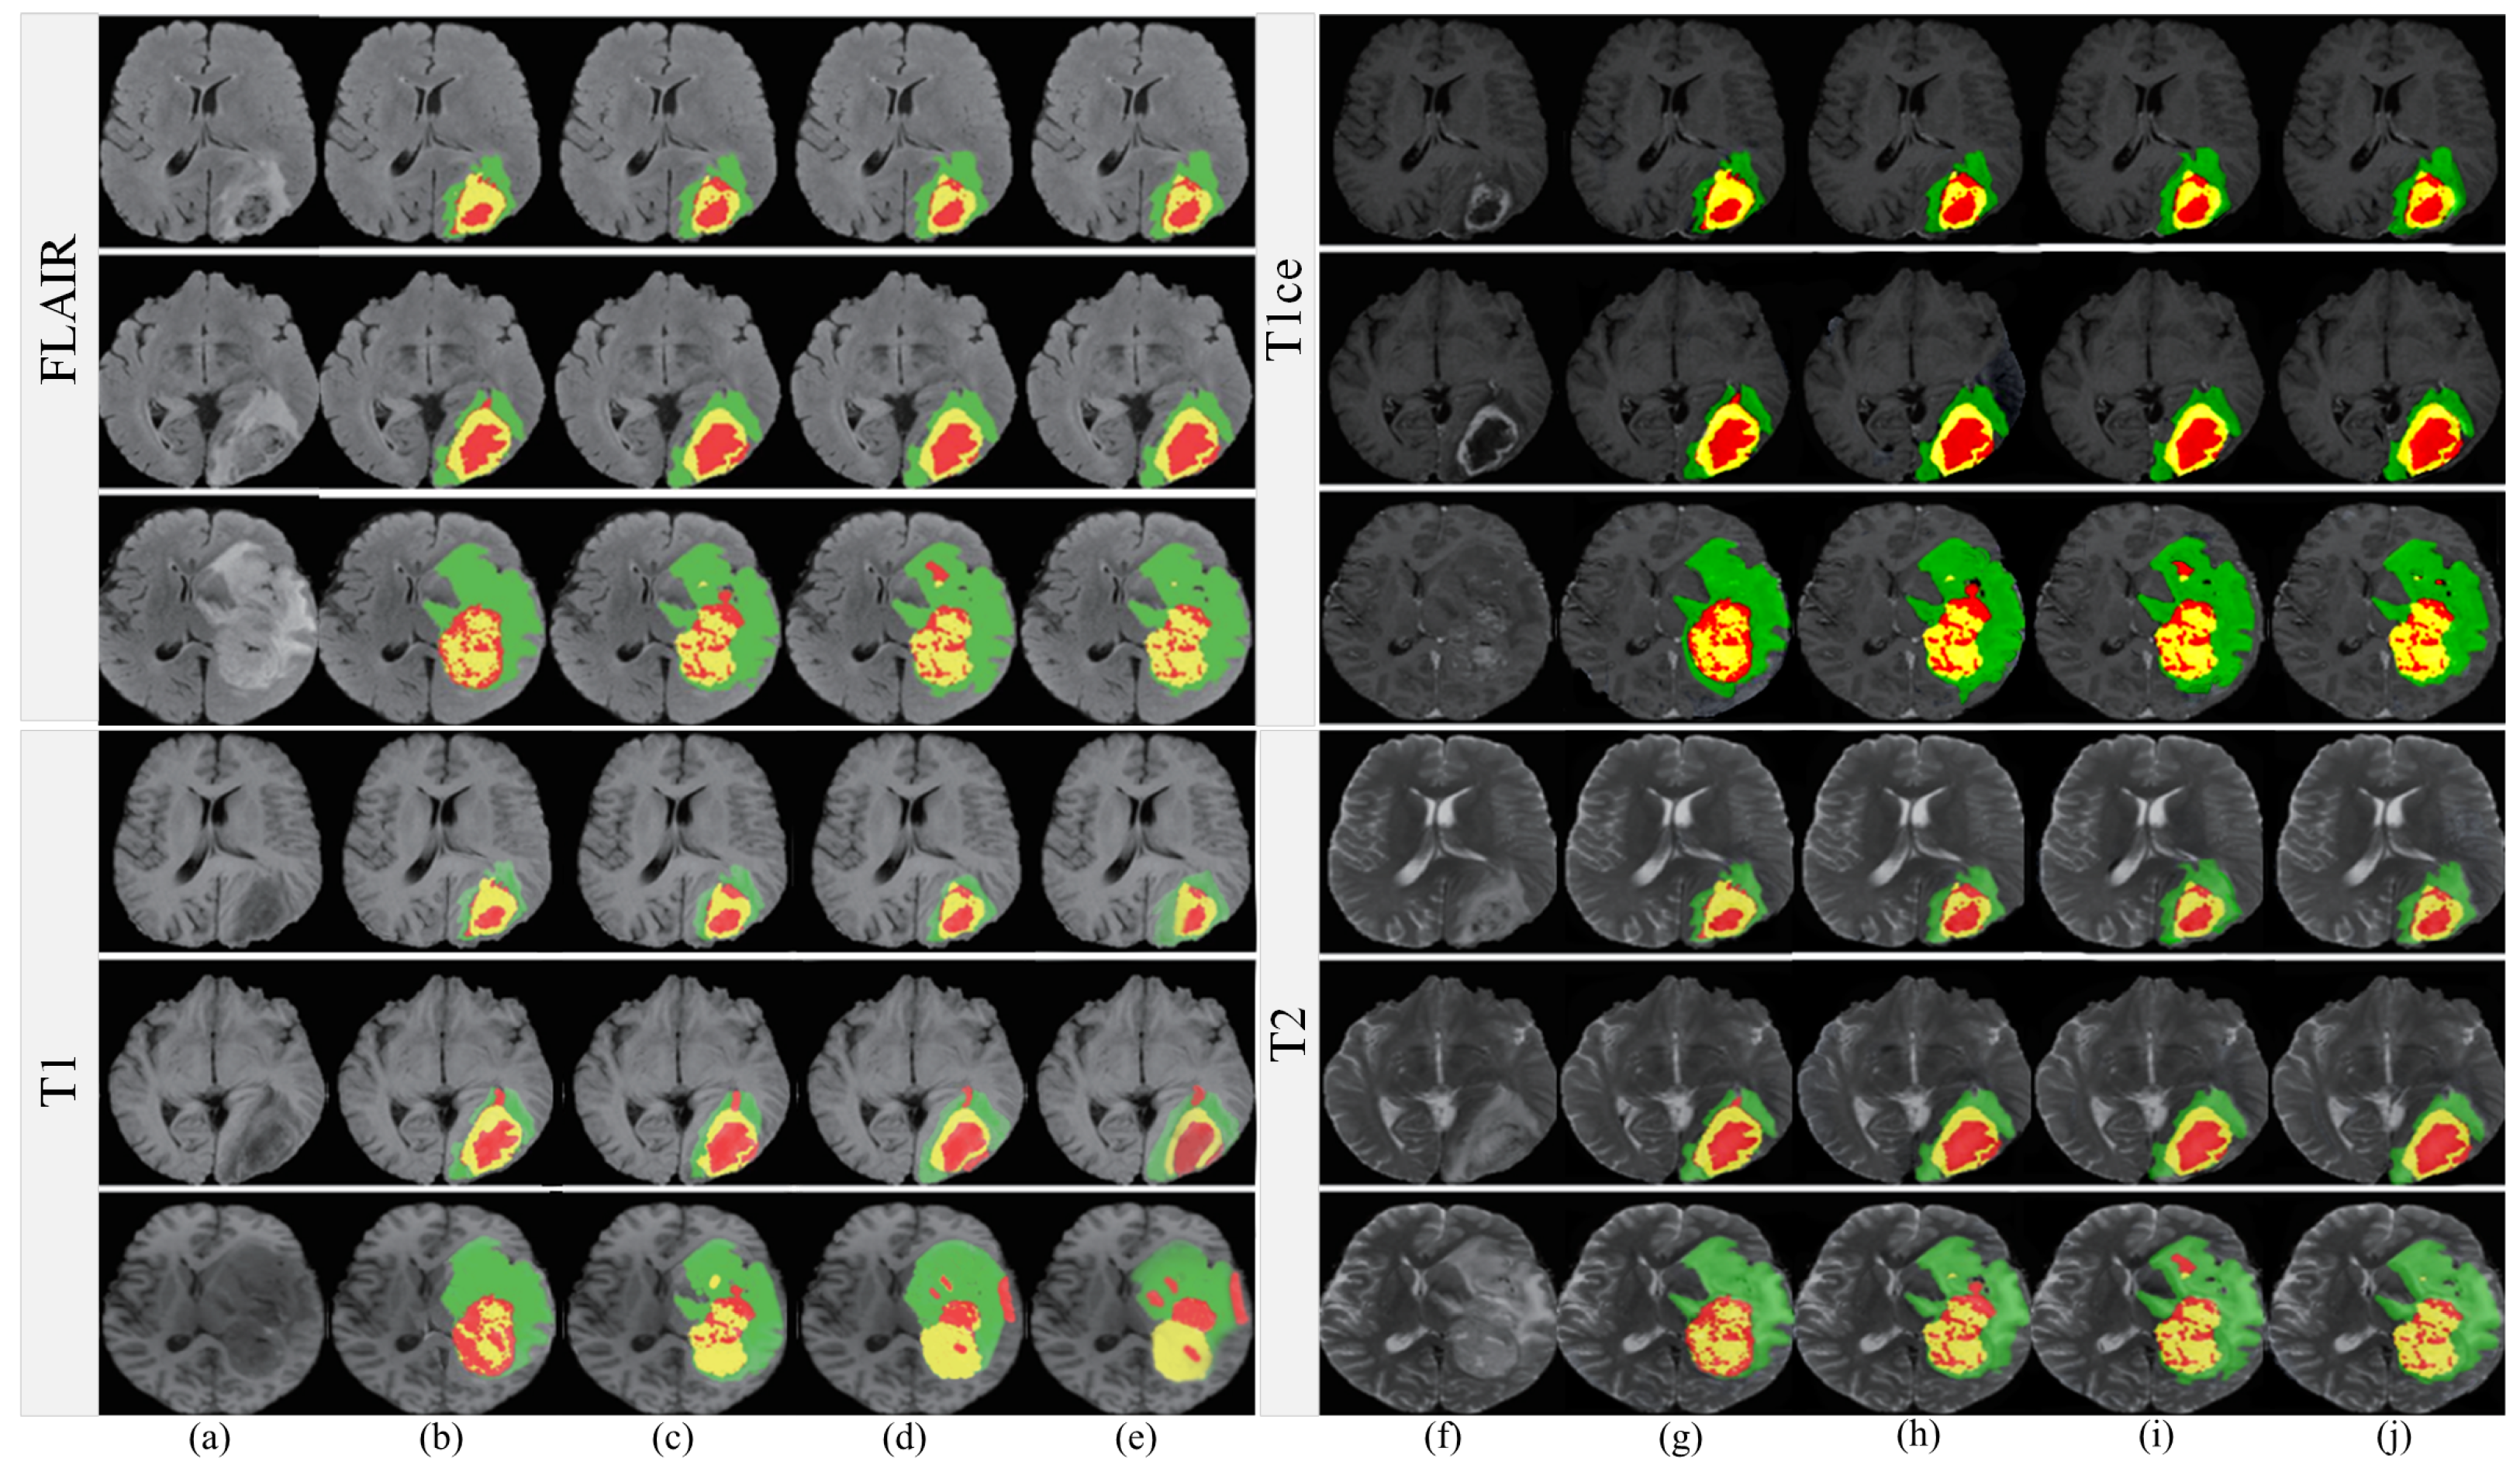

In our current study, aside from the preliminary evaluations that we conducted across various MRI modalities, we devoted particular attention to the FLAIR MRI modality. The selection of this modality is grounded on its prevalent use in brain tumor imaging and characterization. We leveraged the BRATS2019 dataset, a comprehensive and well-annotated dataset that has been recognized as a valuable resource for neuroimaging research, for a more granular and specialized analysis of segmentation performance. The outcomes, meticulously collated, are delineated in Figure 11, a graphical elucidation constructed to facilitate a thorough examination of our empirical observations. When benchmarking against existing state-of-the-art algorithms like 3D-AR [46], DLHT [56], dResU-Net [60], and 3D U-Net [18], a key observation is the conspicuous reduction in false-positive voxels achieved by our proposed methodology. False-positive voxels refer to the misidentification of healthy tissue as pathological, which can potentially lead to overtreatment and is thus a metric of critical significance. This reduction in false-positive rates is not just minor or incidental; it is particularly noteworthy in segments of the MRI scans that are traditionally recognized as challenging for accurate segmentation. These challenging areas include but are not limited to the enhanced and core regions of the brain, where tumor activity and anatomical complexity intermingle. The accomplishment of more precise segmentation in these complex and nuanced areas serves as a testament to the robustness of our algorithm.

Figure 11.

Comparison of segmentation results. (a) FLAIR, (b) T1ce, (c) T1, (d) T2, (e) 3D-AR [46], (f) DLHT [56], (g) dResU-Net [60], (h) 3D U-Net [18], (i) ours, and (j) ground truth.

Furthermore, the remarkable performance gains in these intricate segments of MRI scans are indicative of our algorithm’s capacity to adapt and function effectively even in the most convoluted scenarios. This signifies not only the algorithm’s precision but also its broad applicability and reliability across varying levels of difficulty and complexity in MRI images.